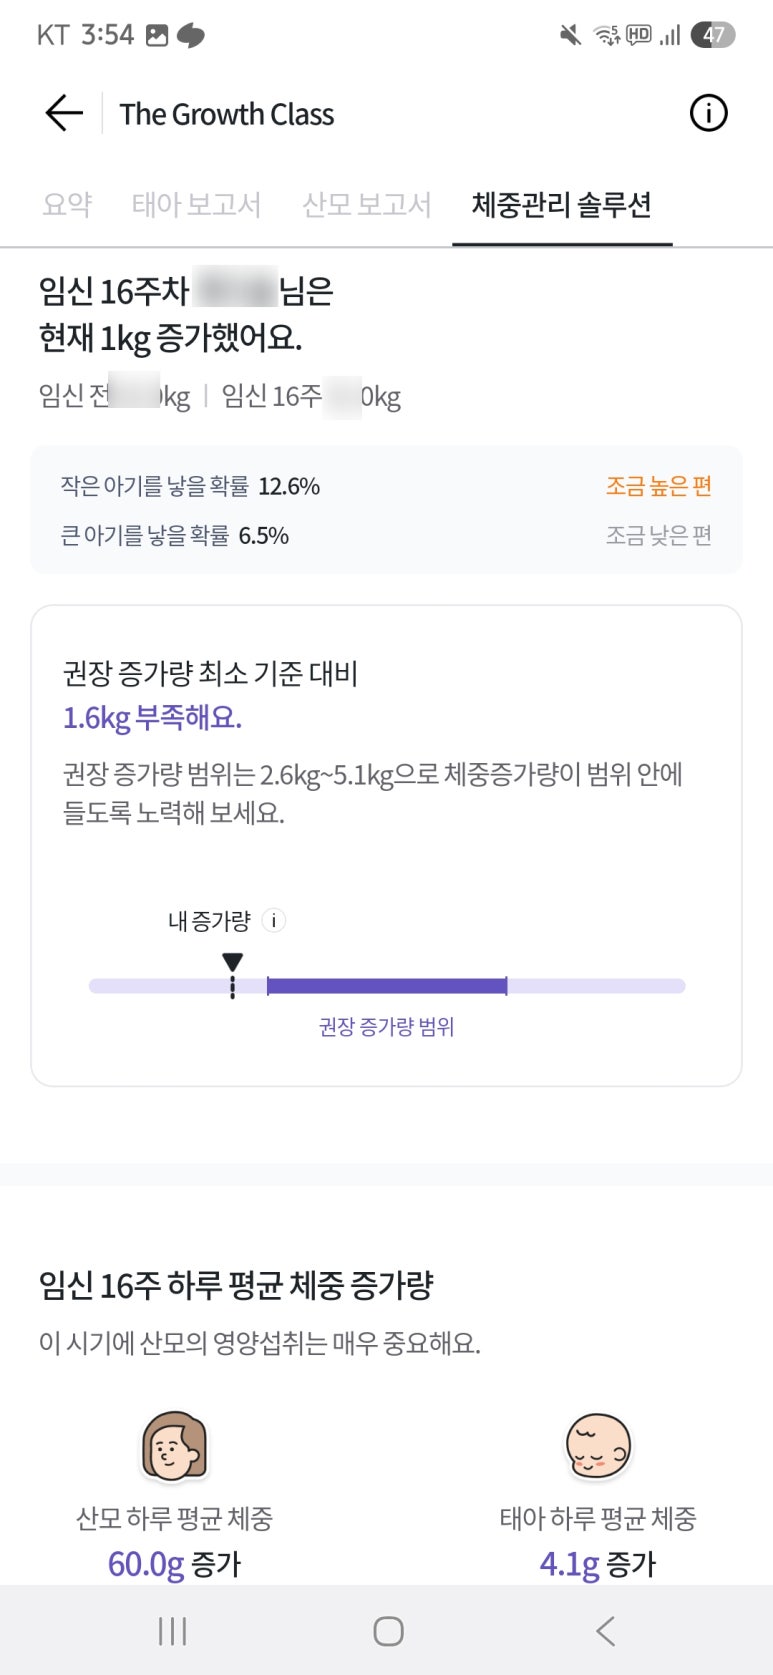

이렇게 아기 머리둘레, 체중이 나올 때는 열달후에 라는 어플에 입력하면

우리 아기와 맞는 주수에 맞는 다른 아기들의 성장도 같이 볼 수 있어서

우리 아기가 어느정돈지 비교할 수 있고

엄마 무게도 비교할 수 있어서 아주 좋아요!

저는 아기가 평균치는 되서 안심했더니 열달후에 들어가니까

같은 주차에 거의 20~30g 차이나는 아기들이 많아서 놀랐어요ㅠㅠㅠㅠ

너무 그동안 내가 안먹었구나.. 우리애가 작구나 싶기두하구...

100명중에 몇번째 이런게 다 쪼끄매서 ㅠ 앞으로 정말 잘 먹어야겠다 생각도 했습니다ㅠ